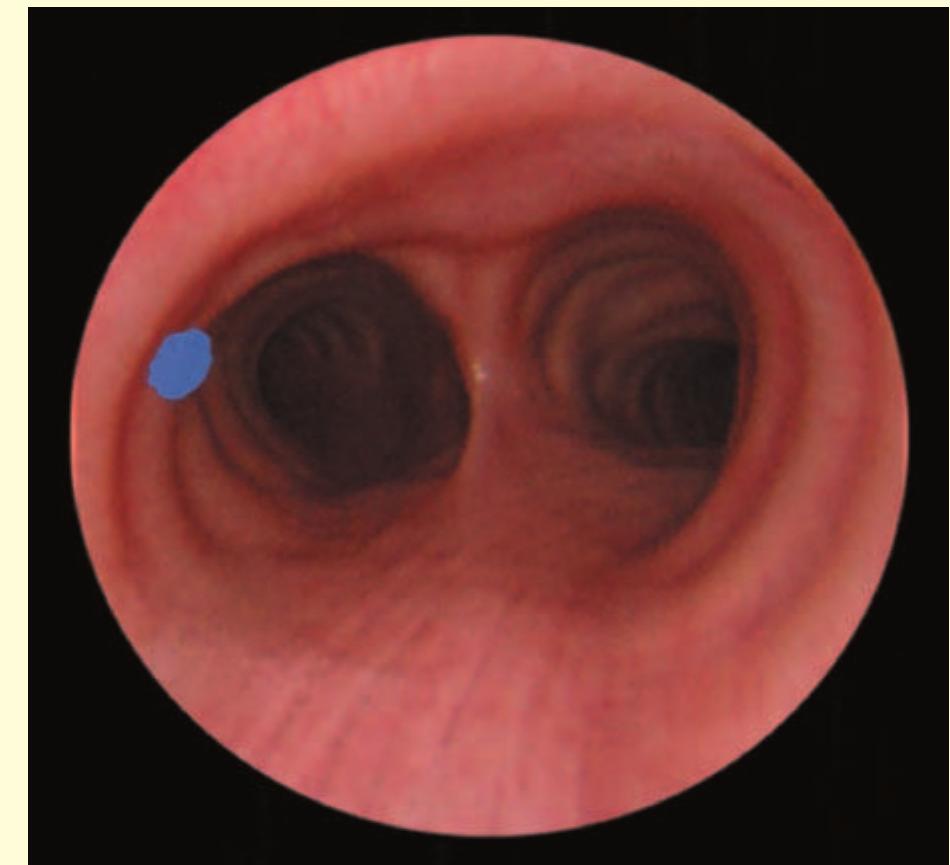

- The bronchoscope is then rotated anticlockwise by 150° to examine the subcarinal lymph nodes (station 7), extending down to the distal margin of the bronchus intermedius.